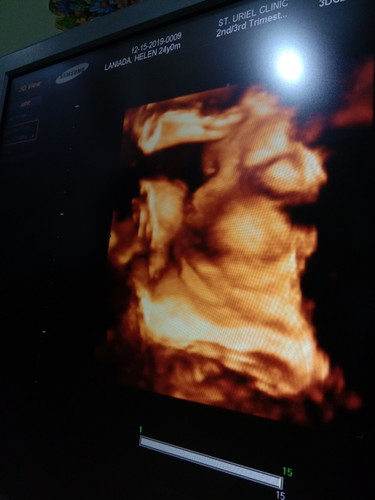

cleft lip

cleft lip po ba ito? nagpa cas na po ako nung 28 weeks na tummy ko wala naman po sya gnyan normal lahat. sa iba po kc ako nagpa 3d . sabi ipa ulit ko dw cas ko. posible po ba cleft lip yn? 34 weeks n po ako now

Hindi naman yata sis, parang mataba lang pisngi ni baby mo kasi yung sakin mataba ang pisngi hehe